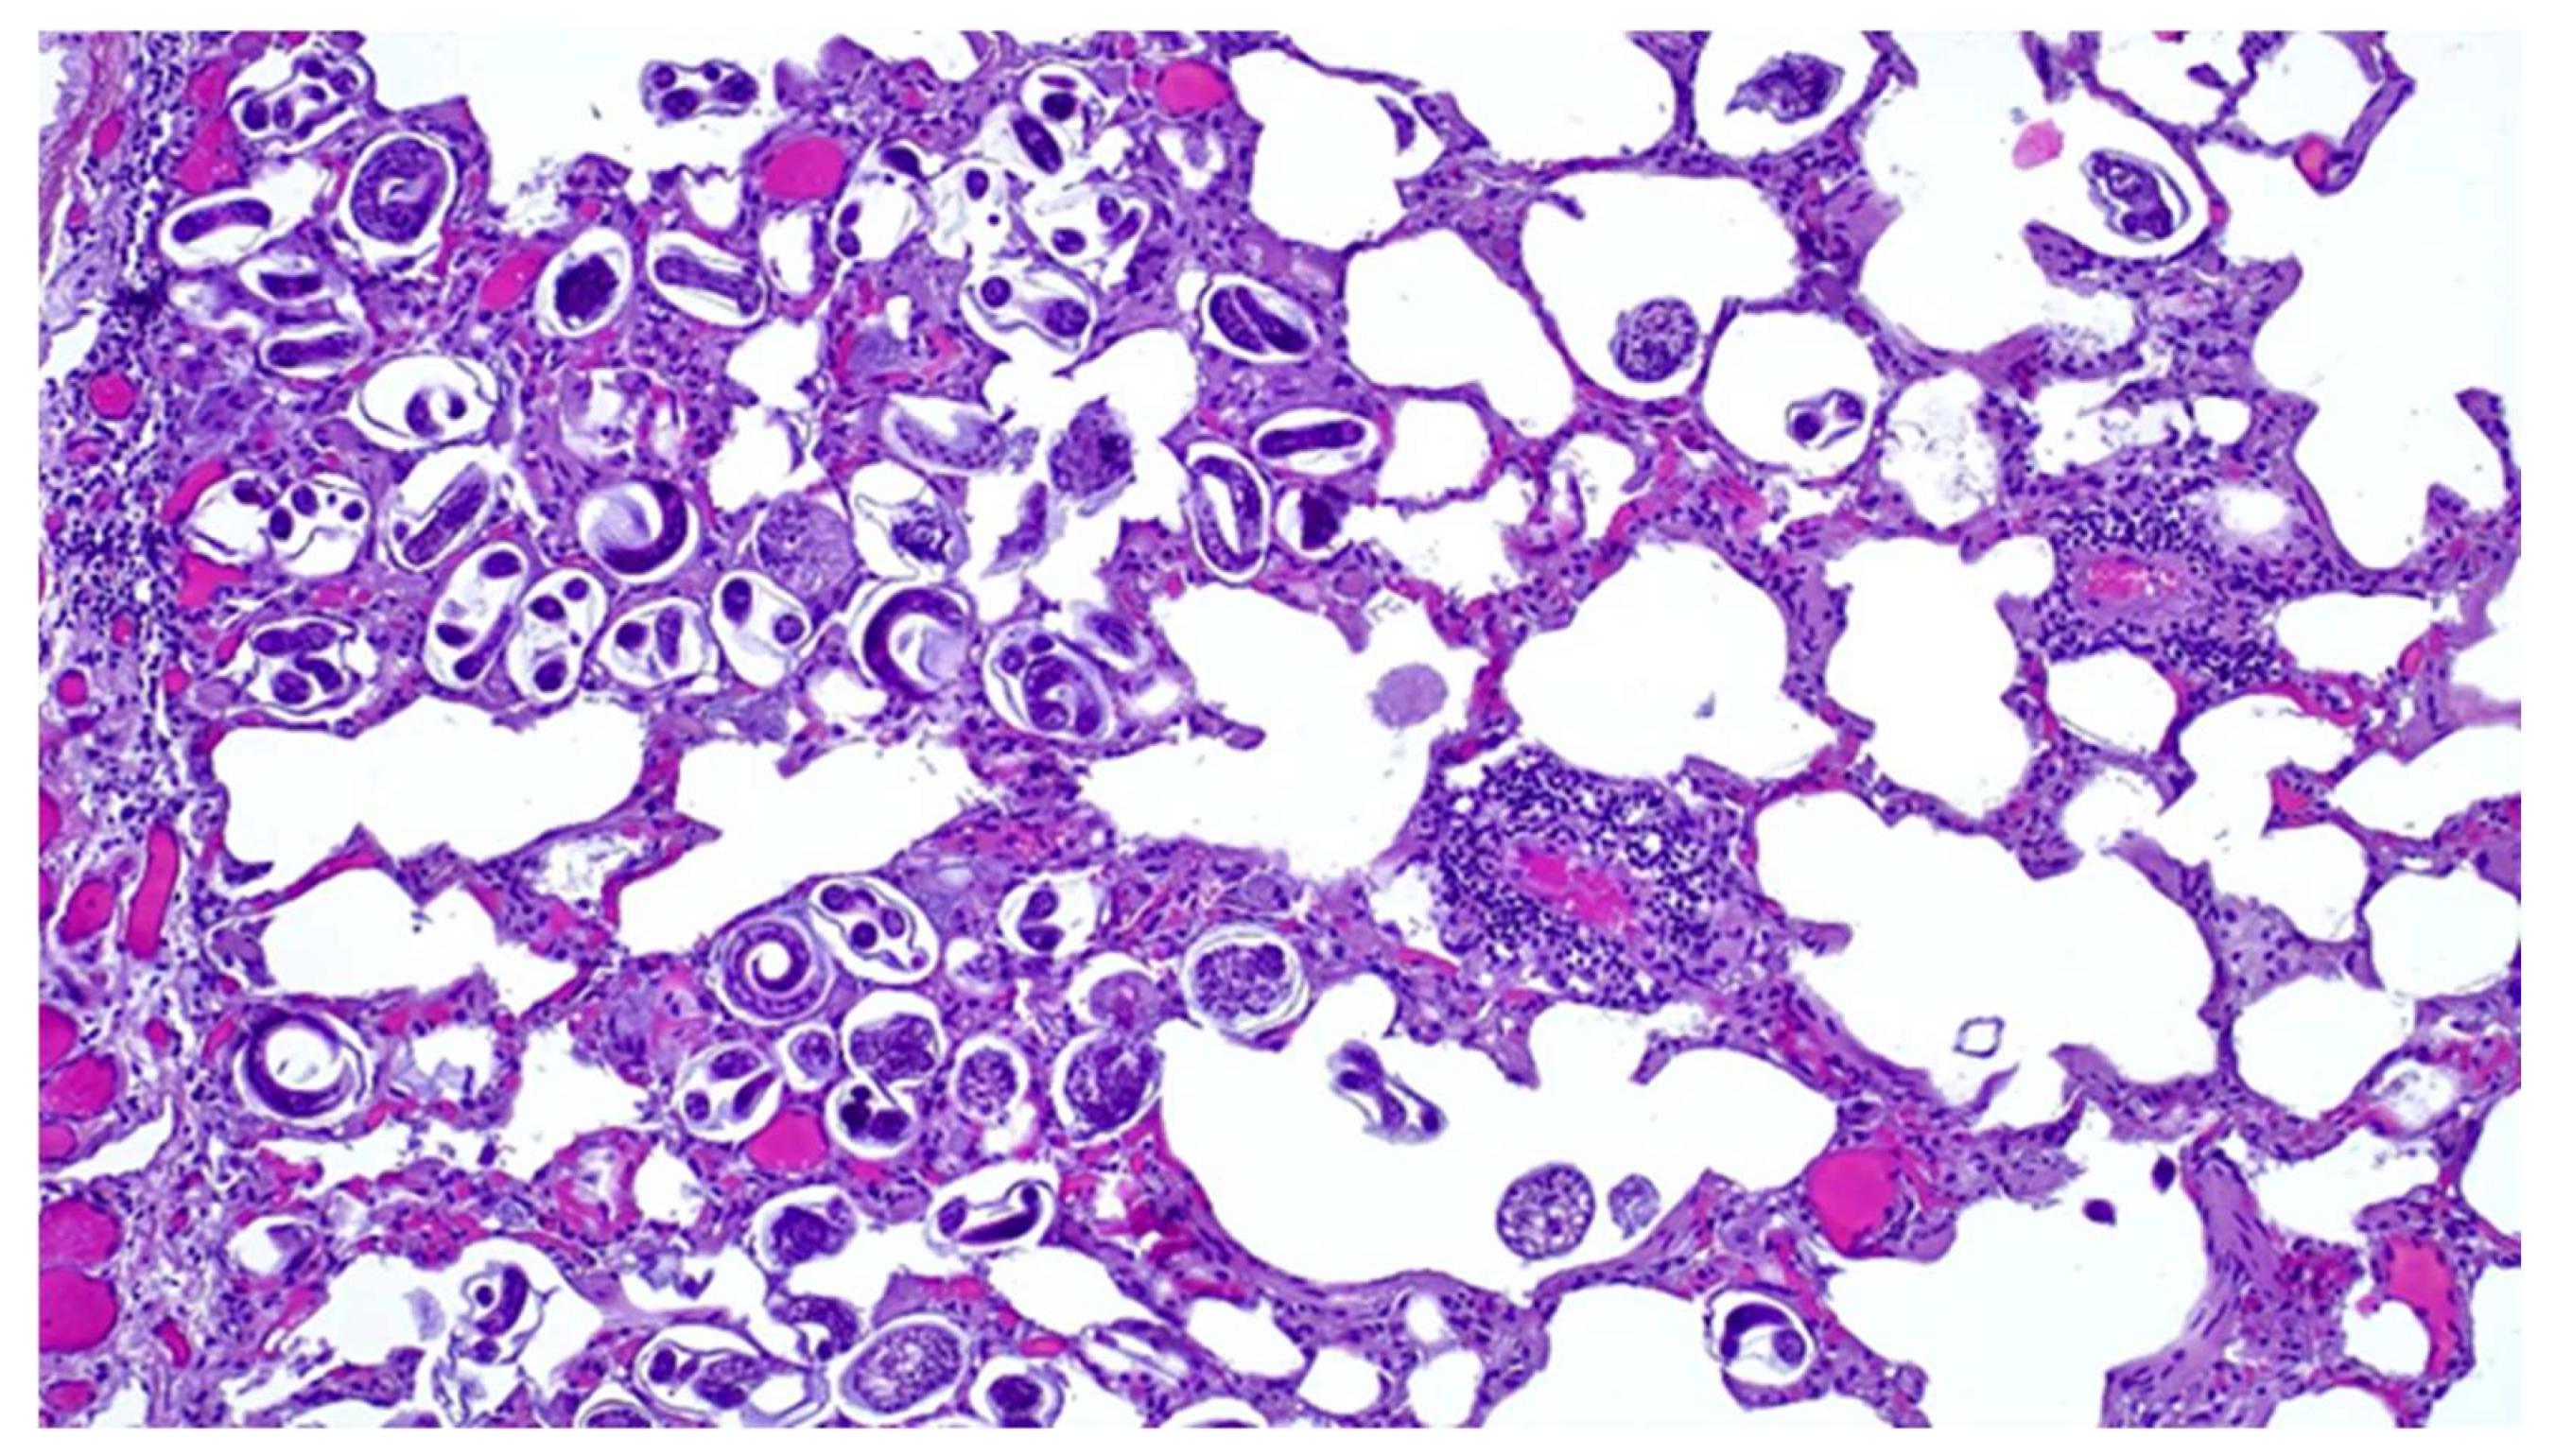

3.3. Microscopic Lesions

Microscopically lung tissue showed a severe parasitic infestation with numerous nematode larvae and eggs present in various stages of development in the bronchioles and the alveolar lumen (Figure 3), consistent with a parasitic bronchopneumonia. A multifocal mild thickening of the alveolar septa, due to the infiltration of macrophages; eosinophils; granulocytes and lymphocytes; hyperemia; the perivascular infiltration of lymphocytes; and peribronchial lymphoid hyperplasia were also observed. Mediastinal lymph nodes showed follicular hyperplasia and the slight infiltration of eosinophil and neutrophil granulocytes, while lymphoid hyperplasia of the splenic white pulp and liver congestion were also observed.

Figure 3. Lung. Histological section. Note the eggs of pulmonary nematodes in various stages of development and first-stage larvae. H&E stain (20×).

Bacterial pulmonary pathology associated with C. pseudotuberculosis is exacerbated by verminous bronchopneumonia related to the presence of high numbers of nematode eggs and larvae, which is particularly severe in the caudal lobes. Several studies have reported a prevalence of Dictyocaulus spp. in the lungs of roe deer in fairly similar climatic areas [,,]. Although the pathogenic significance of nematode infestation in wild ruminants is still controversial, some authors have hypothesized that susceptibility to infestation is closely linked to the poor condition of the animal [], so we could assume that the severity of parasitic pneumonia is related to, or perhaps a contributing cause of, the severely compromised health status of the animal, creating conditions for bacterial dissemination.